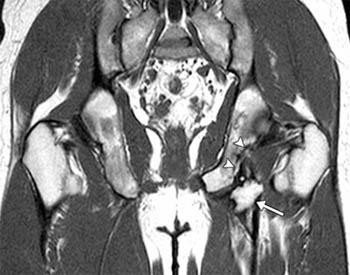

Wrist tendonitis is the inflammation of a tendon within the wrist. Case 2. (A) Coronal proton and (B) axial proton fast spin

Case 2. (A) Coronal proton and (B) axial proton fast spin from www.researchgate.net